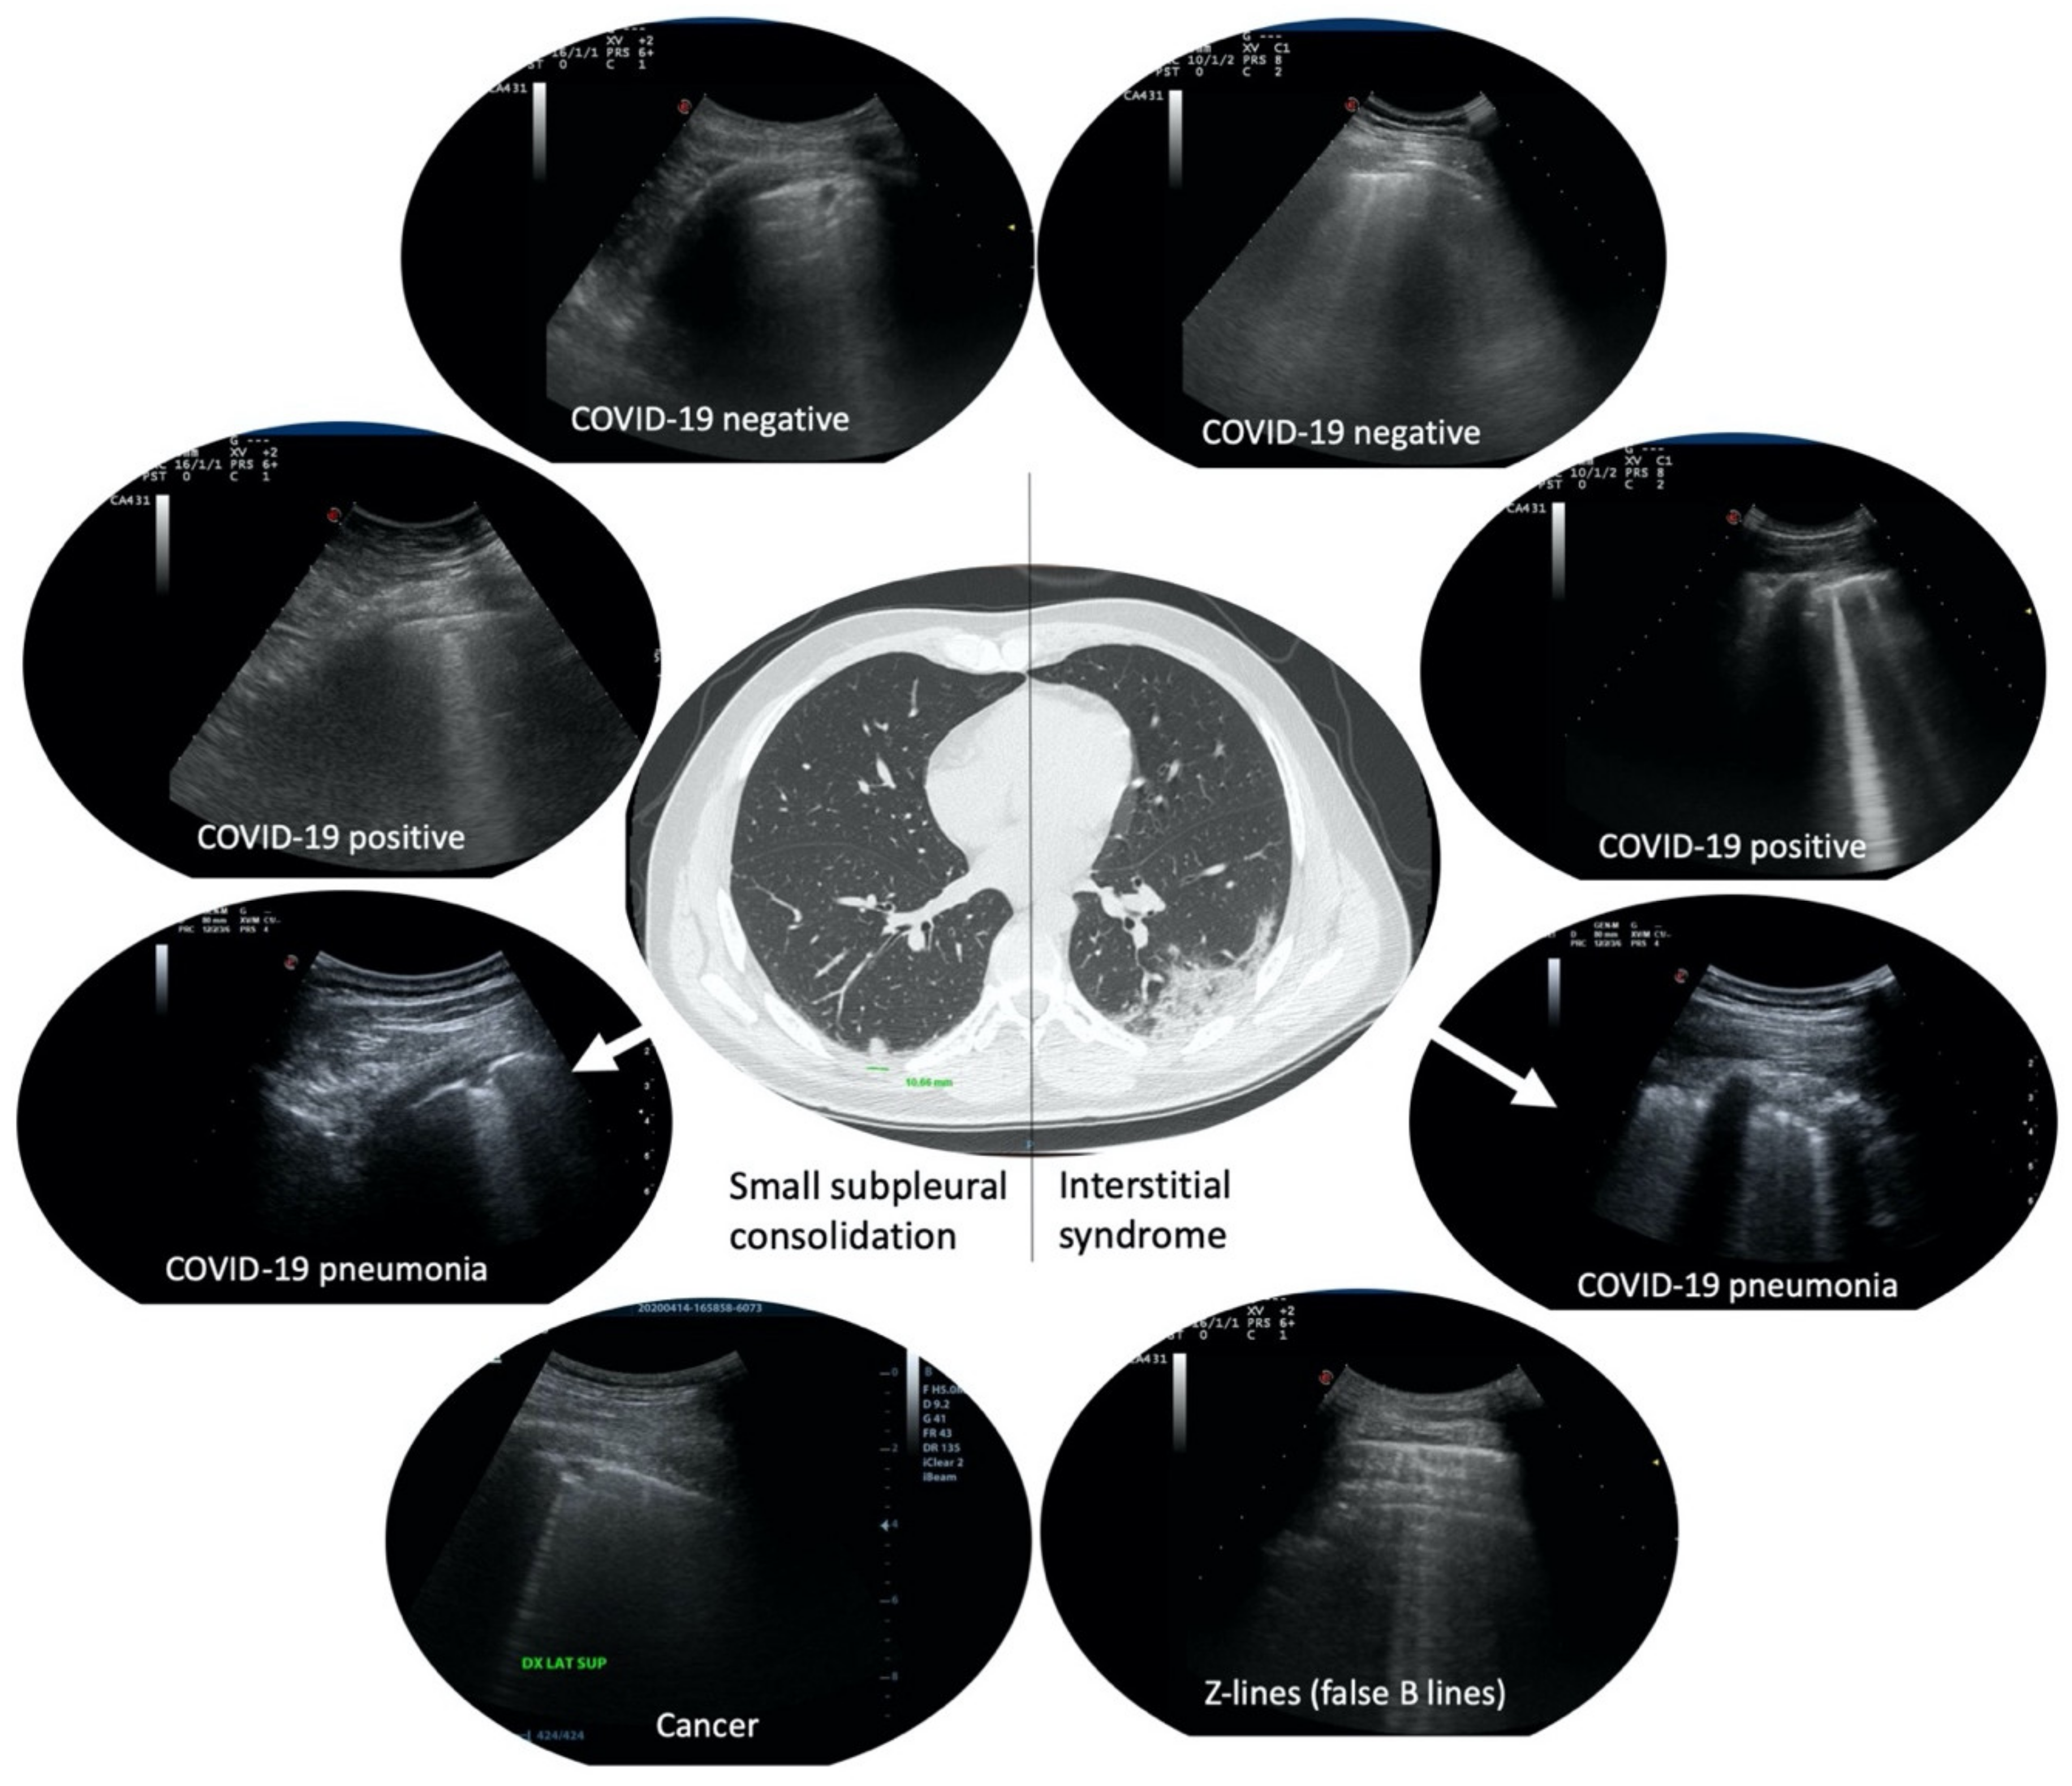

Mono-focal or multi-focal irregular pleural thickening, small subpleural consolidations or group of B-lines, were reported to be indicative of pulmonary involvement in COVID-19 mild to moderate symptomatic cases (Figure 1). This was the case during the peak of COVID-19 pandemic. What it is not well known is the prevalence of these findings in a healthy COVID-19 negative general population. This knowledge is becoming of even greater importance after the first peak of pandemic, in order to avoid misdiagnoses in a situation of endemic disease or of second wave. Prevalence of these findings in non COVID-19 infected patients must be known in order to ascertain the diagnostic role of LU in case of low-moderate pre-test prevalence of the disease. Moreover, specificity and sensitivity of these findings in asymptomatic/pauci-symptomatic, COVID-19 positive, subjects are not well described.

Figure 1. Examples of small subpleural consolidations and group of B-lines more than three per field of scan. In the center, a computer tomography scan of a real COVID-19 patient presenting a small subpleural consolidation in the right lung (left of the image) and a ground-glass area in the left lung (right of the image), and their corresponding features in lung ultrasound (LU) (arrows). On the left, small subpleural consolidations in four different patients with different diagnoses. On the right, group of B-lines more than three per field of scan in four different patients with different diagnoses.

A correlation network analysis was performed in order to visually estimate the relationship between specific lung areas and COVID-19 positivity. LU alterations mostly correlated to COVID-19 positivity were detected in right and left upper-posterior and lower-lateral lung areas (Figure 1 and Table 3).